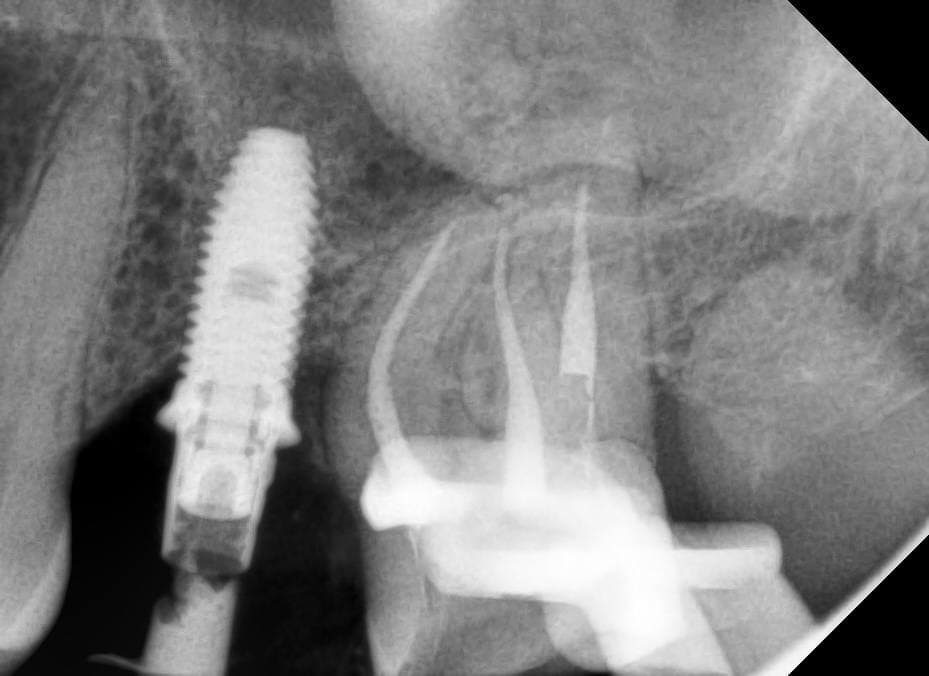

Что у нас было на входе? С правой стороны когда-то были удалены шестой и седьмой зубы, восьмой съехал на место седьмого. С левой — удалён шестой, седьмой с не очень удачно пролеченными каналами, в восьмом огромная полость. Шестой был удалён так давно, что седьмой практически полностью теперь на его месте. Восьмой лежит, не прорезавшийся. Тёмное пятно вокруг седьмого ничего хорошего не говорит, за корнем какая-то проблема локализуется.

Вернёмся к нашей пациентке, у которой процесс удаления восьмёрки стал, к сожалению, более травматичным, чем предполагалось. Врач принимает решение и репонирует отломанный бугор, привинчивая его ортоимплантом. Покажу на снимке: на верхней челюсти, где раньше был восьмой зуб, виден такой контрастный гвоздь. Вот это и есть ортоимплант.

Как так получилось и почему не заметили раньше? Например, почему не увидели на снимке? Здесь нужно понимать, что рентген — это дополнительный метод диагностики. Мы получаем снимок и толкуем, что значат комбинации света и тени на нём. Не всё можно вовремя выявить на снимке — не всё будет очевидно читаться. Поэтому заметить раньше, к сожалению, у нас бы не получилось. Если сейчас, уже задним числом, когда мы знаем, что на этом зубе кариес, вглядеться в снимок и задаться целью найти его в этом самом месте, то можно будет разглядеть намёки. К сожалению, на практике не всегда так срабатывает, что всё можно увидеть заранее.

Последовательные снимки перелечивания корневых каналов седьмого с выявленным дефектом задней поверхности корня